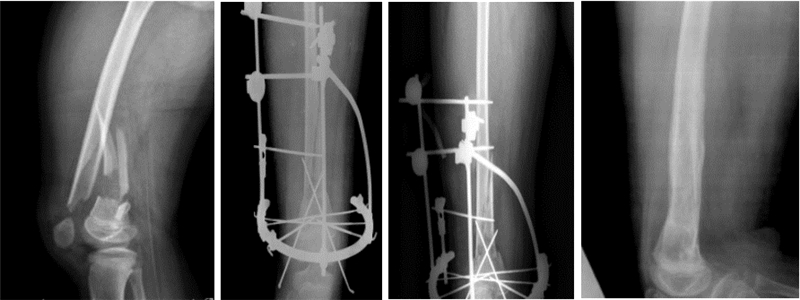

首先麻醉下手法整复骨折,C臂机透视确认骨折复位情况,主要观察骨折解剖力线恢复情况,然后根据复位结果确认下一步治疗措施。如果骨折基本复位或者只残留少许成角畸形,则开始行Ilizarov外固定治疗。固定时根据骨折粉碎情况以及骨折断端离上下关节面远近分别在骨折上下端各一个全环及半环或者两个全环固定。固定时先在远离骨折处上下各行两枚交叉全针,穿针时注意利用肌间隙进入,缓慢进针,局部生理盐水冲洗,减少对血管、神经的损伤,然后用一个全环固定。此时再次C臂机透视以确认骨折复位情况,然后根据骨折稳定性及骨折近远端软组织情况,决定是否再行一个全环或者半环固定(或两半针代替)。如果有粉碎骨折片明显远离解剖力线,则加用一枚橄榄针向力线处牵引后固定[1]。如果骨折闭合整复困难,则在畸形最为明显处行一小切口,然后在尽量不损伤骨膜的基础上整复骨折,再用闭合复位的技巧行Ilizarov外固定。手术结束时常规复查X线,了解骨折复位情况,如果仍有成角等畸形,则再次通过Ilizarov微调技术给予调整到骨折可接受的程度。术后3 d、10 d再次行影像学检查,根据骨折复位情况决定是否再次微调(图 1)。对于粉碎性骨折伴皮肤撕脱需要植皮者,在Ilizarov固定后可以多次清创植皮(图 2)。

图 1 Ilizarov外固定治疗14岁闭合性股骨粉碎性骨折患儿